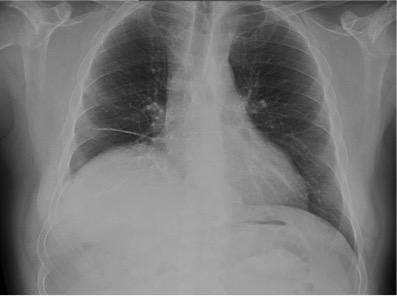

Empecemos, ¿qué ves?

- Comprobar que la placa está bien centrada e inspirada (6 arcos costales anteriores ó 9 posteriores).

- Abdomen y Diafragma

- Partes blandas y estructura ósea.

- Mediastino con silueta cardiaca.

- Parénquimas pulmonares (por separado)

- Comparar un pulmón con otro.

Seguir esta sistemática, dejando el pulmón para el final no nos olvidaremos de lo más importante.

Regla: Acaso Tiene Mucha Patología Pulmonar (Abdomen, Tejidos blandos y hueso, Mediastino, Pulmón por separado, Pulmón bilateral)

Nota: ¡¡¡No olvidar la placa lateral!!! La regla a seguir es la misma. Leer abdomen y diafragma, examinar parte posterior, tejidos blandos y subir por la columna; tráquea y descender por mediastino. Finalmente pulmones.

Solución: Es un estudio Normal. Silueta cardiomediastínica y parénquimas pulmonares sin alteraciones significativas.